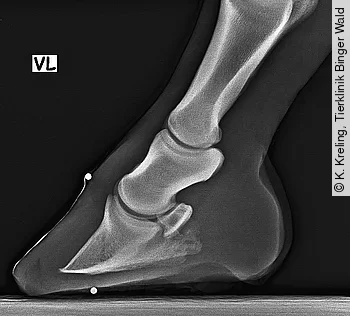

Die Durchführung standardisierter Röntgenaufnahmen der Zehe stellt die Basis für Therapie und Prognose dar. Während eine Rotation des Hufbeins oftmals erfolgreich therapiert werden kann, hat die Senkung des Hufbeins eine deutlich schlechtere Prognose. Die Röntgenbilder sind auch hilfreich, um ein akutes von einem eher chronischen Geschehen zu unterscheiden.

Bei den Röntgenaufnahmen der Zehe ist auf eine abnormale Breite der weißen Linie und die dorsale Ausziehung des Hufbeins (sog. Hutkrempenbildung) zu achten.

Die orthograde lateromediale Aufnahme (Abb. 4) ist wichtig, um die Position des Hufbeins in der Kapsel zu erfassen. Eine dorsopalmare/-plantare Aufnahme kann lateromediale Imbalanzen bei chronischer Hufrehe feststellen. Bei starken Veränderungen der Hornkapsel sollte der Huf vor dem Röntgen bearbeitet werden, um eine unregelmäßig lange Zehe nicht mit einer Rotation des Hufbeins zu verwechseln.

Das Standardisieren der Röntgenaufnahmen beinhaltet das Setzen von röntgendichten Markern am Kronrand (Ansatz der letzten Haare), der dorsalen Hufwand und der Spitze des Strahls an der Sohle. Somit können die Dicke der Sohle, der Abstand des Proc. extensorius vom Kronrand (Rehestrecke), die Hufwanddicke und eine Rotation gemessen werden. Die Aufnahme sollte 90° zur Gliedmaße, mit dem Fokus zwischen Hufspitze und Ballen, circa 2 cm distal des Kronrands angefertigt werden.